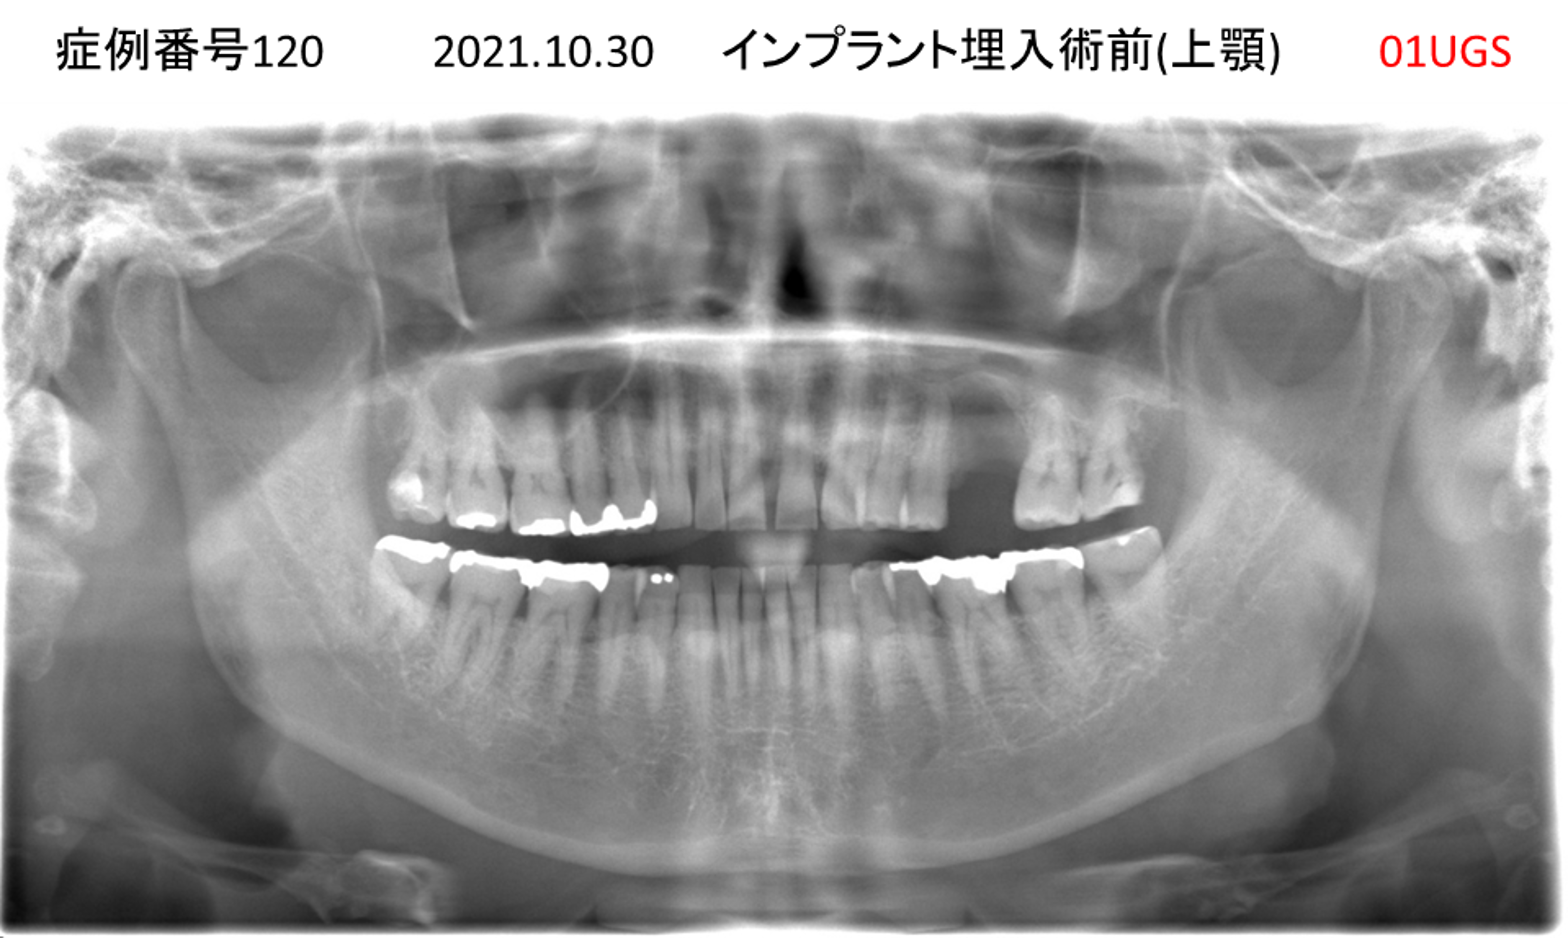

上の前歯が揺れてきてかめない患者様のインプラント症例

| 治療名称 |

インプラント |

| 治療費用 |

335万円+税 |

| 治療期間 |

4か月 |

| 患者さんの症状(主訴) |

上の前歯が揺れてきて噛めない |

| 治療内容 |

サイナスリフト 抜歯即時インプラント |

| 治療結果 |

ちゃんと噛めるようになった。不安がなくなった。見た目がとても良くなったのすごくうれしい。 |

| 治療の注意点(リスク/副作用) |

インプラントが壊れたら再治療が必要 |